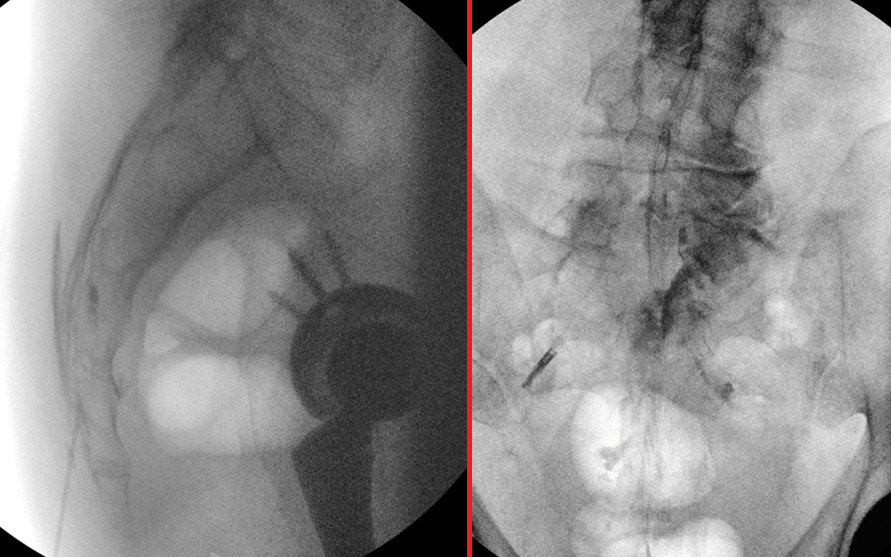

An example of the procedure, including fluoroscopic images demonstrating needle placement through the sacral hiatus and contrast spread following catheter advancement to the right L5/S1 region, is shown below in Figure 1.

The left image presents a lateral fluoroscopic view, demonstrating the advancement of an 18-gauge Tuohy needle through the sacral hiatus for caudal epidural access. The right image displays a post-contrast anteroposterior (AP) fluoroscopic view, showing the contrast spread after a 21-gauge epidural catheter was directed toward the right L5/S1 region, confirming targeted medication delivery.